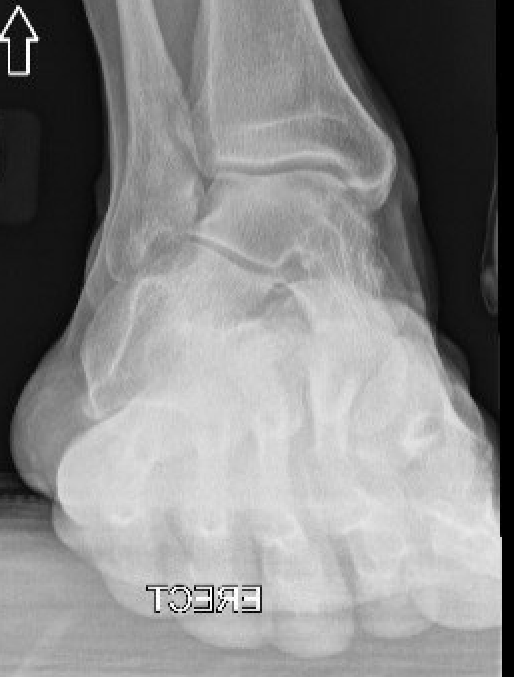

AP weight bearing of ankle

Early - calcaneus under lateral malleolus

Late - valgus tilt of talus with ankle joint osteoarthritis